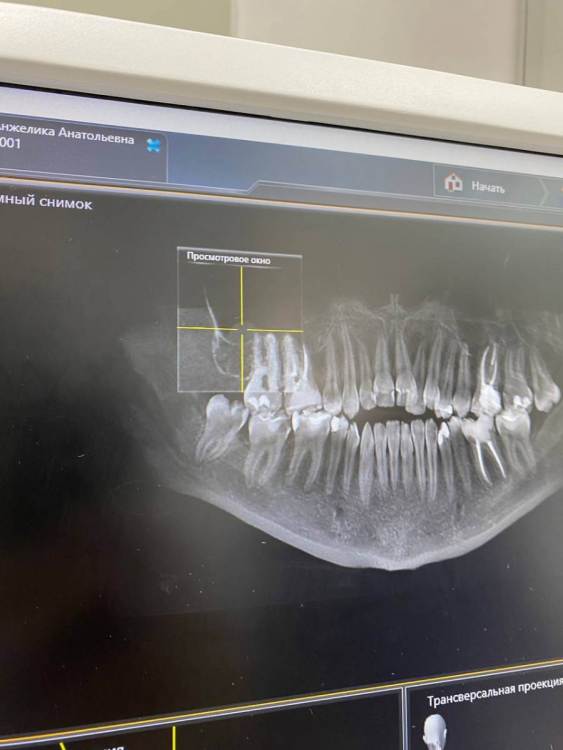

Здравствуйте. В начале марта я сходила на прием, была пролечена (депульпированна) верхняя правая шестерка. После установки временной пломбы в течение двух недель не прекращались ноющие ощущения, поэтому было решено с врачом перелечить зуб. Зуб перелечили, но ноющие боли по-прежнему остались. Зуб не реагирует на холодное/горячее, не шатается, однако реагирует на постукивания.

Была у лора, в одной пазухе есть полип. Может ли он влиять на зуб? Также была у окулиста и невролога с целью исключения патологии тройничного нерва. С этим все в порядке.

Два дня назад треснула эмаль зуба и врач хочет поставить все-таки временную коронку. Я пока сомневаюсь и честно говоря не знаю, что делать, потому что эти странные ноющие ощущения в зубе по-прежнему актуальны. Да и как ставить коронку на зуб, который болит от того, что по нему стучат?...

Была уже у трех врачей, но все говорят, что зуб запломбирован нормально и четкого ответа никто дать не может.

Буду благодарна за любую помощь и ответ. photo_2023-08-09_18-14-31.thumb.jpg.e23f86db67c6866262d362dc6a8b8242.jpgphoto_2023-08-09_18-14-29.thumb.jpg.b2e19e72b9027bf4e4a44185f0ca97e4.jpgphoto_2023-08-09_18-14-25.thumb.jpg.afbef81bf80ad897dc7ffd28efc2453a.jpg

photo_2023-08-09_18-14-28.jpg